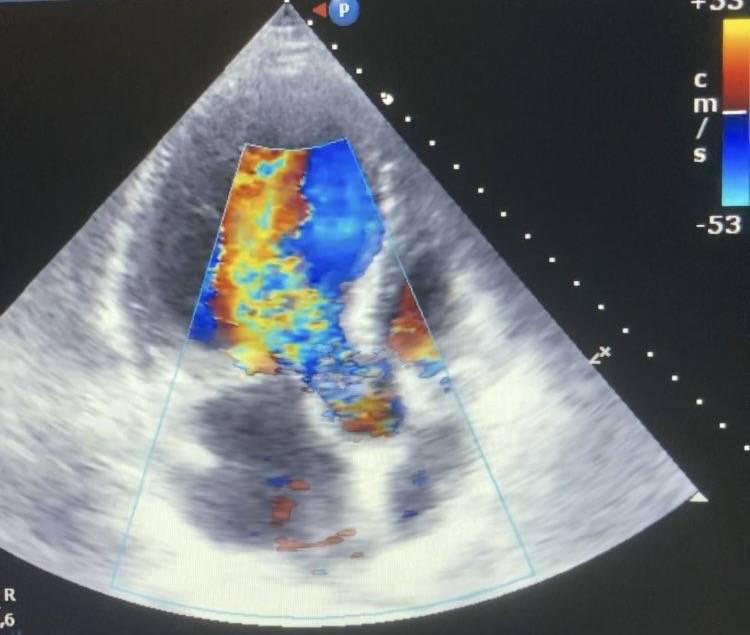

Tras realización de analítica con leucocitosis con desviación izquierda, radiografía de tórax anodina y sin otro foco infeccioso aparente se decide ecocardiografía a pie de cama.

Descripción de los hallazgos ecográficos y las imágenes más relevantes para la resolución del caso

En hemocultivos se detecta Streptococcus anginosus que inicialmente se trata con antibioterapia intravenosa. En TC se visualiza gran verruga en válvula aórtica con insuficiencia severa asociada, por lo que se decide cirugía preferente para recambio valvular.

Ante la presencia de un paciente con clínica inespecífica sin foco infeccioso claro la ecocardiografía a pie de cama ha resultado de gran utilidad para fundamentar la sospecha diagnóstica.